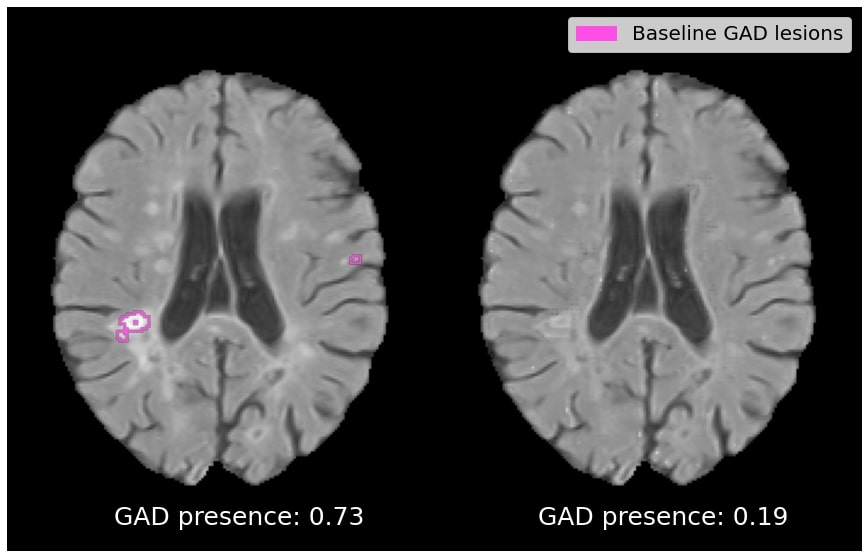

Target Class Similarity Quantitative results depicting the average T2 lesion volumes and Gad lesion prevalence for the reconstruction and generated counterfactual image are reported in Table 2. For comparison, we also include T2 lesion volume and Gad lesion prevalence statistics for real active and real inactive samples. In the top row, we see that the average T2 lesion volume of the reconstruction is relatively close to that of the real active samples. On the other hand, the average T2 lesion volume of the counterfactual is substantially lower, being closer to the T2 lesion volume of the real inactive subjects than the active subjects. A similar trend can be observed for Gad lesion prevalence, where the Gad prevalence of the generated counterfactual has dropped closer to the prevalence observed among real inactive subjects. Overall, these results show that the counterfactual images are realistic in terms of their ability to discover clinically established population-level predictive markers, without a priori knowledge of these markers. In this case, this leads to a reduction in baseline T2 lesions load and a removal of baseline Gad lesions from the counterfactual images.

Figure 4 depicts qualitative results for the effect on T2 and Gad lesion load. In (a), we show an example of a patient with above-average lesion load, with the counterfactual exhibiting a 79% drop in T2 lesion load. In (b), an active patient is shown with a below-average lesion load (i.e. an example that goes against the population-level trend), with the counterfactual exhibiting a 54% drop in T2 lesion load. In (c) and (d), the counterfactual images exhibit a complete suppression of Gad lesions. Overall, Gad lesions are suppressed to a much greater extent than T2 lesion suppression. This aligns with the statistics for real active and real inactive populations (see Table 2).